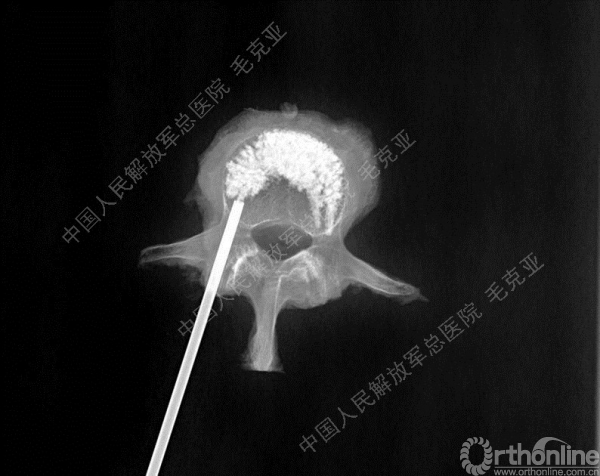

导语:随着社会老龄化的不断加速,骨质疏松性椎体压缩骨折作为一种普遍存在的老年骨科疾病已经成为现今骨科界的一个热点话题。传统的保守疗法治疗效果不佳,而现有的椎体增强技术又具有多种风险和缺陷。针对这种现状,中国人民解放军总医院毛克亚教授提供了一种新的解决方法。